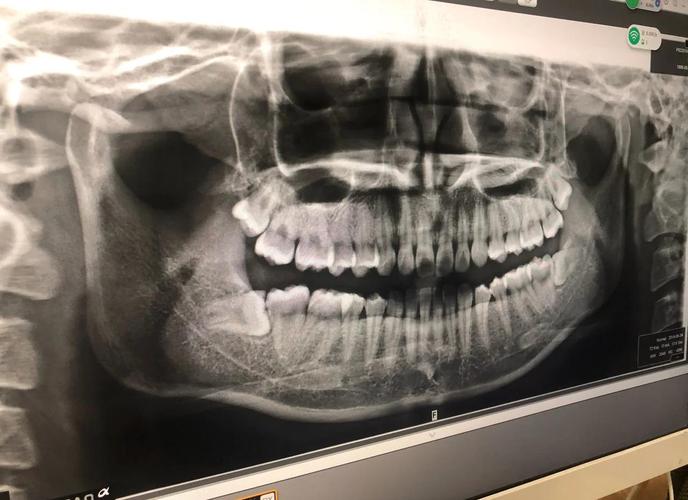

智齿(第三磨牙)通常在17-25岁萌出,由于人类颌骨退化,多数人颌骨空间不足以容纳智齿正常萌出,导致其出现阻生、倾斜、部分萌出等情况,这类智齿可能从多方面干扰正畸效果:

- 空间侵占与牙齿拥挤:阻生智齿可能向前挤压,推挤前牙牙弓,导致正畸排齐后的牙齿再次出现拥挤,影响稳定性。

- 邻牙损伤风险:部分萌出的智齿易食物嵌塞,滋生细菌,引发邻牙(如第二磨牙)龋坏、牙周炎,甚至导致邻牙牙根吸收,直接破坏正畸基础。

- 咬合干扰与颞下颌关节问题:异常萌出的智齿可能形成早接触点,干扰咬合平衡,长期可能引发颞下颌关节紊乱,表现为关节弹响、疼痛等。

- 正畸中后期意外萌出:若正畸前未拔除智齿,治疗过程中智齿可能突然萌出,占据正畸所需空间,导致方案调整、治疗周期延长,甚至影响最终咬合关系。